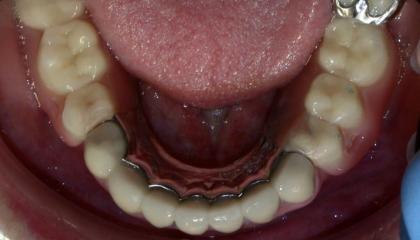

Before